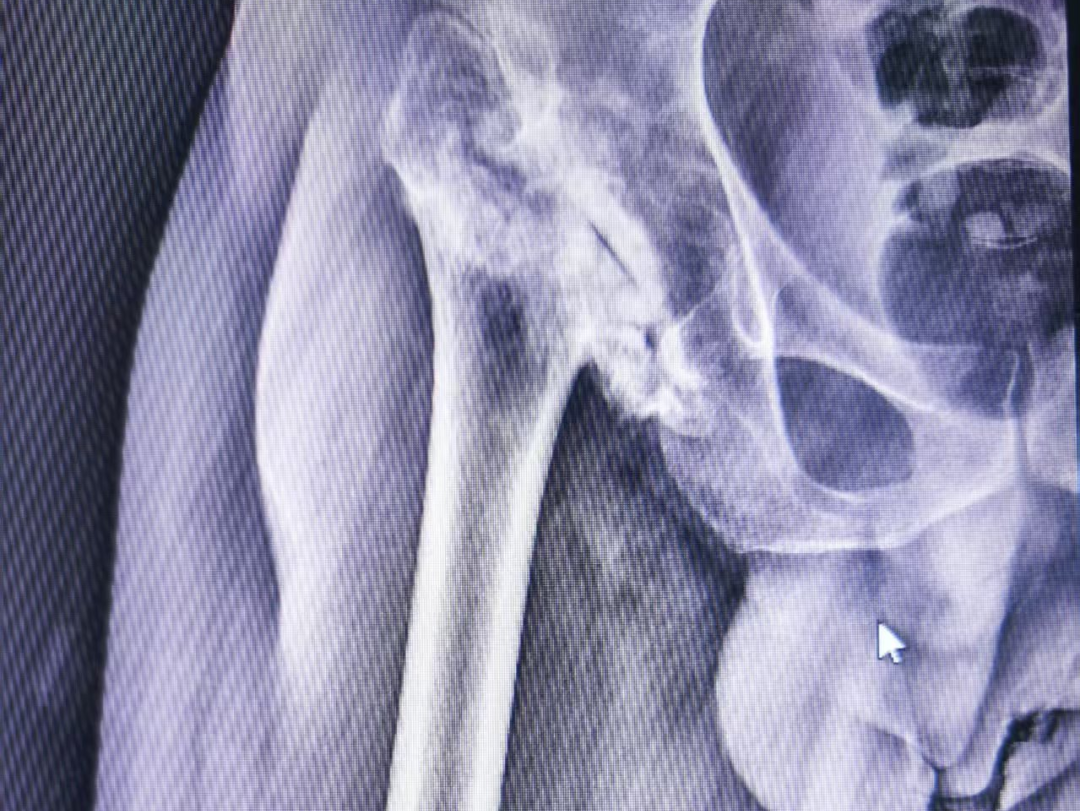

检查发现,种先生髋关节股骨头缺失,大结节严重上移,肌肉紧绷,关节结构紊乱,手术难度极大。

二是巧解难题:精准术前设计,重塑髋关节,下移大结节恢复力学平衡。

三是松筋活络:术中精细松解挛缩肌肉,保护神经血管。